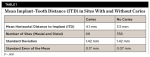

Horizontal distance from the implant platform/abutment connection to the adjacent tooth: The data indicates that as the distance between the natural tooth and the implant increases, the incidence of decay increases precipitously (Figure 2 and Figure 3). Decay occurrences range from 7.4% when the implant-tooth distance (ITD) is <2 mm to 40% when the ITD is ≥6 mm. In the 69 sites that exhibited caries, the mean ITD was 4.1 mm, and in the 338 sites without decay the mean ITD was 3.5 mm (P = .005) (Table 1). A logistic regression was performed with the single binary variable indicating whether or not the "horizontal threshold distance" was greater than 4 mm. The results show a statistically significant odds ratio of 2.00 (95% confidence interval of 1.191599, 3.350288) (Table 2.) Therefore, it is suggested that the horizontal threshold of 4 mm be considered as the "critical ITD."

Vertical distance from the interproximal contact area to the implant platform: This measurement varied greatly among samples and showed not to be a statistically significant contributing factor in decay formation (Table 2).

Presence or absence of restorations on the adjacent teeth: A positive correlation between existence of a previous restoration and decay was found (Figure 4, Figure 5, and Table 2).

This study strongly suggests that there is a direct correlation between the horizontal ITD and incidence of decay. The 17% incidence (range = 7.4% to 40%) of caries formation on the 407 sites was significantly higher than normal incidence of root caries (1.87% to 2.7%) previously reported in the literature.2,3 It can be inferred from this data set that an ITD of <4 mm is recommended to significantly reduce the likelihood of developing caries in teeth adjacent to molar implants. Additionally, the data suggests a statistically significant correlation between the presence of a previous restoration on the natural tooth and caries formation. However, this data should be considered with caution as not all decay occurred directly at the restorative margin, but rather some decay occurred distant to the margin, further apically on the root surface.